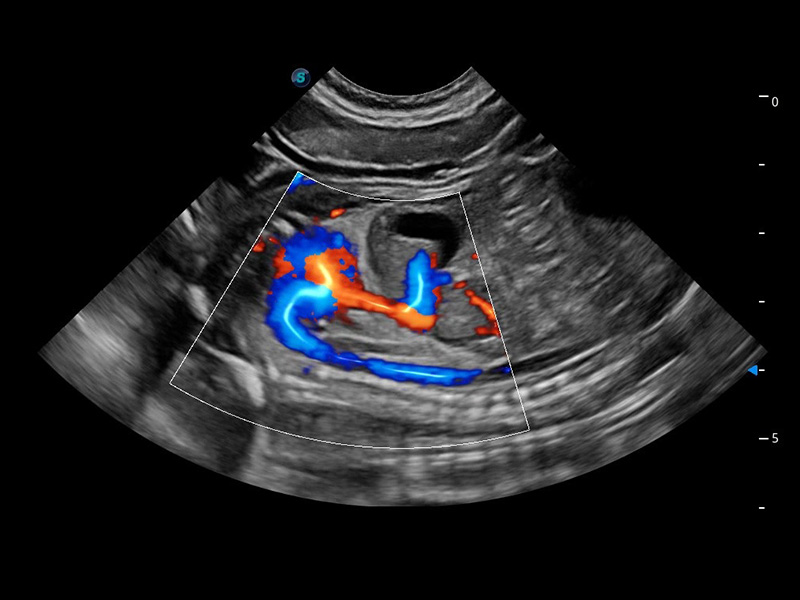

(貓)髂動(dòng)脈血流頻譜